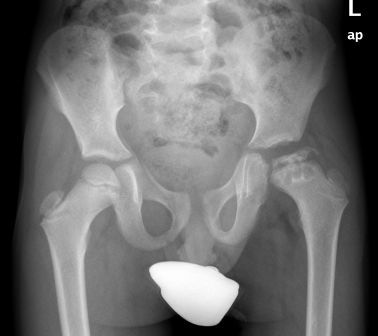

Hình 7. Bệnh nhân bị bệnh Perthes – Hoại tử chỏm xương đùi trái.

Sử dụng Nẹp chỉnh hình với vành đỡ PTF trong điều trị nhằm giảm tì đề nên khớp háng.

Hình 8. Bệnh nhân bị bệnh Perthes-Hoại tử chỏm xương đùi trái.